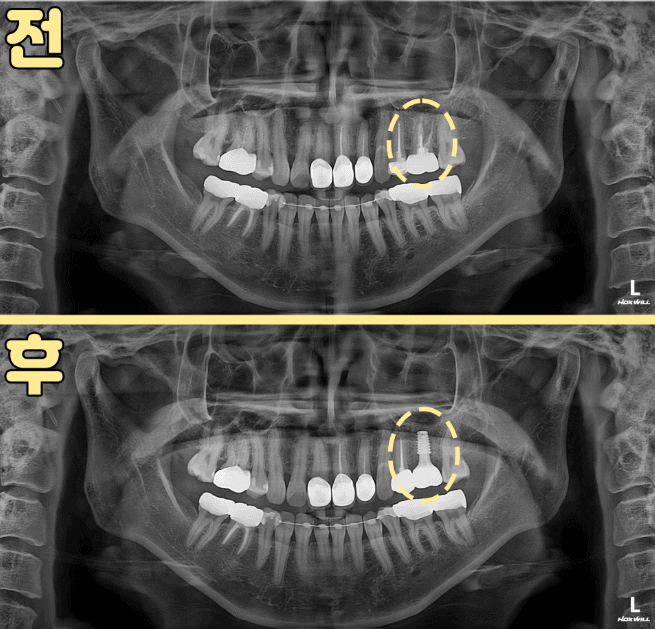

40대 여성 환자분은 2년 전 하악 어금니 치료 후 크라운을 사용 중이셨습니다.

최근 딱딱한 음식을 씹을 때 불편함이 생겨 내원하셨는데요.

일반 엑스레이에서는 특별한 이상이 보이지 않았지만, 3D CT에서는 뿌리 끝에 염증이 확인되었습니다.

미세현미경으로 기존 크라운 내부를 들여다보니 충전이 완전하지 않은 근관이 있었고, 그 틈으로 세균이 다시 들어간 흔적이 보였습니다.

정밀 장비와 경험이 없다면 놓치기 쉬운 부분이죠.

기존 충전물 제거 → 철저한 소독

재신경치료는 기존 충전재를 제거하는 단계부터 시작합니다.

하지만 딱딱하게 굳은 재료를 치아 벽을 상하지 않게 제거하는 것은 상당히 숙련된 기술이 필요합니다.

저희는 초음파 기구와 미세 파일, 그리고 20배 확대 미세현미경을 사용해 남아 있던 충전재와 세균을 꼼꼼하게 제거했습니다.

그 후 근관을 넓혀 소독액으로 여러 차례 세척하고, 1주일간 임시 약제를 넣어 염증이 가라앉은 것을 확인한 뒤 최종 충전을 진행했습니다.

이 과정은 **“세균이 다시 번식할 틈을 절대 만들지 않는다”**는 원칙으로 진행됩니다.

완전한 밀봉 + 새 보철물 제작으로 마무리

기존 크라운에서는 미세한 균열이 확인되어 재감염 위험이 있었기 때문에 새로 제작했습니다.

단순히 씌우는 것이 아니라, 치아와 보철물이 하나처럼 밀착되도록 정밀하게 제작하여 세균 침투 가능성을 차단했습니다.

3개월 뒤 추적 검사에서 뿌리 끝 염증이 사라졌고, 6개월·1년 경과에서도 안정적으로 유지되었습니다.